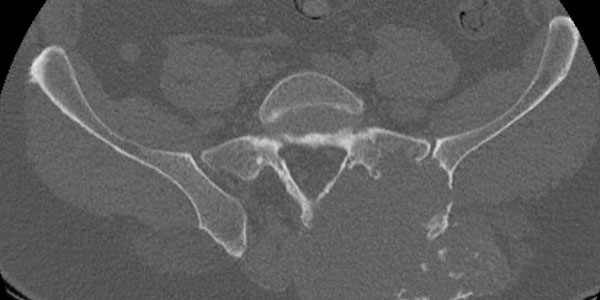

Kondrosarkom - Kıkırdak Doku Kaynaklı Kemiğin Kötü Huylu Tümörü

Kıkırdak doku kaynaklı kemiğin kötü huylu tümörüdür. Sıklıkla 40 yaş sonrası ortaya çıkar. Erkeklerde daha sık görülür. En sık pelvis, kalça ve omuz çevresinde saptanır. Uzun kemiklerin sıklıkla metafiz bölgesinde yerleşir.